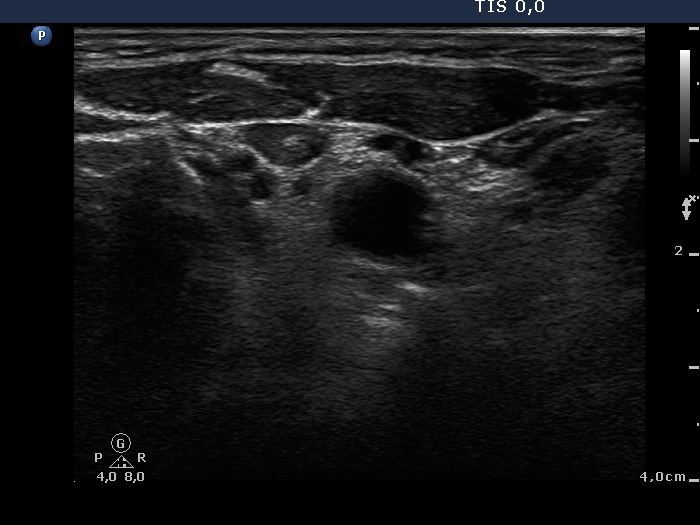

Papillary carcinoma - Case 4. (ultrasonographic picture 11)

Left side of the neck, above the thyroid, horizontal scan. There is a lymph node with intact hilum.